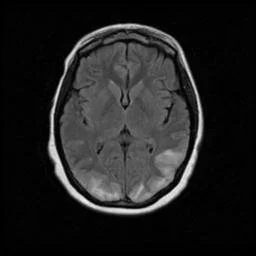

Posterior Reversible Encephalopathy Syndrome (PRES)

• Basically posterior circulation is not able to respond to changes in blood pressure and symptoms result

• Associated with high blood pressure (may seen in eclampsia/pregnancy)

• Can also be seen with chemo use - specifically cisplatin and cyclosporine

• Vision issues (hence posterior) and encephalopathy

• Imaging Findings

• Bilateral vasogenic edema of occipital & parietal lobes

• T1 hypo, T2 hyper

• Everything is vague - may restrict/but also may not, may enhance/ but also may not, may have microhemorrhages/ but also may not

• MRA - vessel irregularities, vasoconstriction

• Treatment - treat underlying cause, manage BP